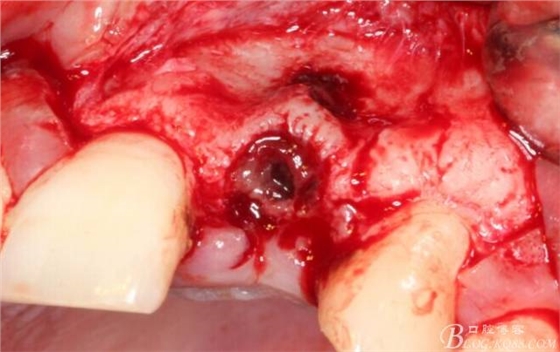

于是我果斷告知患者,手術(shù)失敗了,不能拖延,如不及時(shí)處理,炎癥繼續(xù)發(fā)展會(huì)很快波及鄰牙牙槽骨?;颊呓邮芪业慕ㄗh。切開(kāi)翻瓣,骨粉及生物膜消失了,骨吸收嚴(yán)重,幸運(yùn)的是,因?yàn)樘幚砑皶r(shí),鄰牙骨支持依然存在。

徹底掻刮。